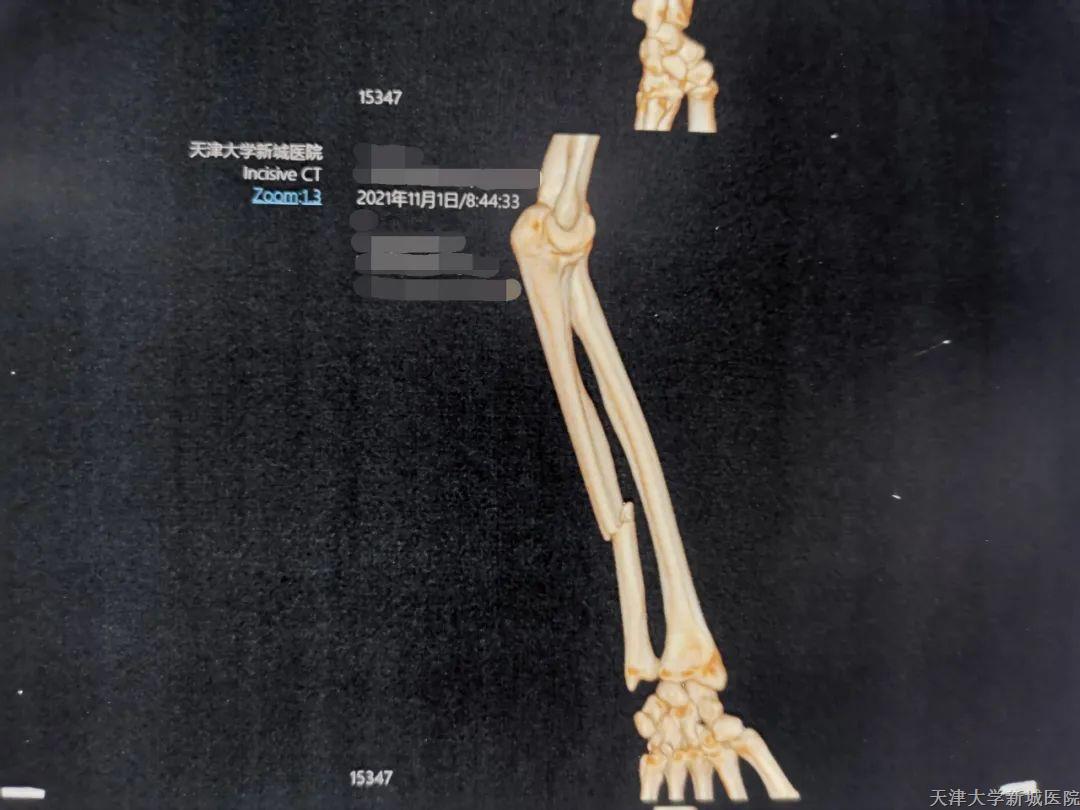

患者邓女士,因意外损伤左侧前譬及左眼,但神志清楚,查体配合,来我院急诊就诊,经过尺桡骨平扫3D-CT检查后,术前诊断为左侧尺骨骨折,于10月29日收入院进行手术治疗。